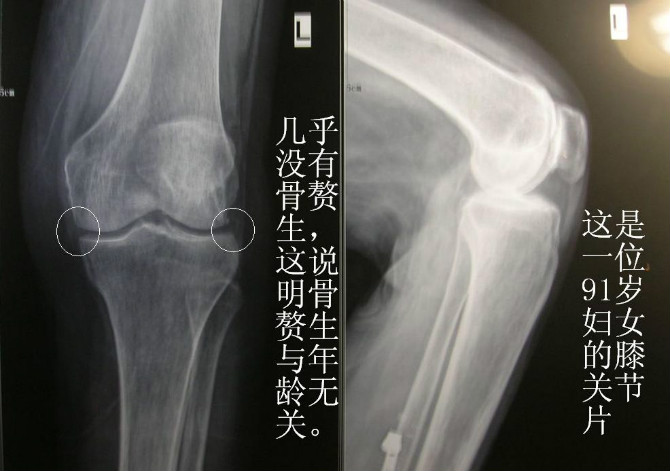

我用脊柱上形成的過(guò)程來(lái)說(shuō)明。我們脊柱的發(fā)育早期是軟的脊索。脊索分節(jié)后,每一節(jié)里有幾個(gè)骨化中心。骨化中心擴(kuò)大融合就形成椎骨。椎骨把脊索沒(méi)有骨化的部分?jǐn)D成餅狀,就是椎間盤,脊索中央組織就是間盤的髓核。脊索膜變成脊柱的前、后縱韌帶和椎骨膜。前縱韌帶與間盤連接致密,后縱韌帶與椎體連接緊密,連接的強(qiáng)度是不同的。腰椎的活動(dòng)范圍是向前和左右,只有特殊訓(xùn)練的人才有向后的活動(dòng)。當(dāng)我們?cè)谪?fù)重的情況下反復(fù)向前和左右彎腰時(shí),腰椎的椎體緣擠壓間盤組織,就會(huì)產(chǎn)生小的損傷,損傷就會(huì)出血,出血會(huì)沿韌帶和骨膜向椎體中間漫延。這時(shí)候我們會(huì)感到腰部酸痛。漫延的血腫機(jī)化,鈣質(zhì)沉著就變成骨組織。當(dāng)人們年輕時(shí),修復(fù)能力強(qiáng),勞累引起的酸痛經(jīng)過(guò)一夜的睡眠就會(huì)恢復(fù)。機(jī)化血腫的骨化也就逐漸形成,這是一個(gè)經(jīng)年累月的過(guò)程。早期機(jī)化的血腫是透X線的,所以看不出椎骨的變化。經(jīng)過(guò)若干年后再攝片,就看到“骨刺”了。這也就是為什么人到中年以后攝片能看到骨刺的原因。當(dāng)間盤組織水分減少,變“脆”后,反復(fù)活動(dòng),使間盤邊緣損傷,形成血腫和鈣化,上下兩個(gè)椎體之間就會(huì)出現(xiàn)鷹嘴樣骨贅生,繼續(xù)損傷、修復(fù)就會(huì)形成骨橋甚至融合。可以這樣說(shuō),中年看到的“骨刺”是二十歲是強(qiáng)體力工作的結(jié)果;老年看到的骨橋,是中年仍從事強(qiáng)體力工作的結(jié)果。頸部的骨刺形成機(jī)理和腰椎相似。是頭部反復(fù)前屈、左右屈形成的。這也是為什么椎體的增生都在椎體上下緣并且是在前和左右形成的原因。隨著社會(huì)的發(fā)展,強(qiáng)負(fù)重的勞動(dòng)減少,骨質(zhì)增生的人會(huì)減少的。并不是40歲以上,90%的人有骨質(zhì)增生。一輩子不做負(fù)重的人,就是活到90歲,在其X線片上也很難看到大的增生。

再說(shuō)說(shuō)膝關(guān)節(jié)骨刺形成的過(guò)程。我們的任何活動(dòng)都是與損傷修復(fù)伴隨的。負(fù)重的情況下膝關(guān)節(jié)的過(guò)度活動(dòng),對(duì)軟骨和骨面都是損傷,軟骨的損傷最先出現(xiàn)。這包括關(guān)節(jié)面軟骨和半月板。而這些組織是填充在關(guān)節(jié)內(nèi),減緩沖擊力和減輕摩擦的。一旦損傷,會(huì)出現(xiàn)關(guān)節(jié)不穩(wěn)定,行走時(shí)就會(huì)出現(xiàn)微小的晃動(dòng),關(guān)節(jié)的骨緣就要受傷,產(chǎn)生血腫,機(jī)化后鈣質(zhì)沉著,膝關(guān)節(jié)“骨刺”就這樣誕生了。這樣的骨刺也是沿著關(guān)節(jié)軟骨和膜下形成的,肉眼所見,也很光滑,不會(huì)引起疼痛。而這些增生的骨質(zhì)多在膝關(guān)節(jié)兩側(cè),說(shuō)明膝關(guān)節(jié)不穩(wěn)定,行走時(shí)左右晃動(dòng)是引起損傷的原因。早期攝片也是看不出的。等到看出來(lái),也反復(fù)疼了若干年了。兒童子也會(huì)出現(xiàn)這樣的修復(fù)。經(jīng)常有兒童夜間膝關(guān)節(jié)疼痛,沒(méi)有紅腫,經(jīng)過(guò)一夜睡眠就好了。那為什么兒童到長(zhǎng)成都看不到增生?因?yàn)閮和歉稍谏L(zhǎng),修復(fù)的骨組織融和在骨干中了。再說(shuō)說(shuō)膝關(guān)節(jié)髕骨緣的骨刺形成過(guò)程。這和跟骨骨刺的形成過(guò)程相同。都是腱附著處的損傷修復(fù)。因?yàn)閾p傷在附著處,血腫沿著腱的膜漫延。漫延的血腫機(jī)化后鈣質(zhì)沉著形成骨組織。????綜上骨刺形成經(jīng)過(guò)的說(shuō)明,可以得出結(jié)論,第一骨刺不是病,更不是疼痛的原因,而是曾經(jīng)有過(guò)的(很早以前)疼痛的結(jié)果。第二骨刺形成是骨修復(fù)后形成的瘢痕,不是骨退行性改變。骨的退行性改變是骨的萎縮,所謂的生理性骨質(zhì)疏松。所以大可不必談“骨刺”色變,以為得了什么不治之癥。更有“醫(yī)生”甚者要手術(shù)切除“骨刺”,不是可笑么?看到上述“骨刺”形成的原理,你就知道怎樣避免骨刺形成了,也知道頸部反復(fù)活動(dòng)的保健操是給自己的未來(lái)制造“骨刺”了,是不可取的。也有人說(shuō)骨刺壓迫血管,壓迫神經(jīng)可以引起疼痛。這也是說(shuō)不通的。從前述我們知道“骨刺”是由血腫來(lái)的。血腫是軟的,不是它壓迫神經(jīng)、血管,而是相反,鈣質(zhì)沉著是沿著受壓成形的血腫進(jìn)行的,怎么會(huì)壓迫神經(jīng)、血管呢?在脊柱,神經(jīng)都是在椎體后面出來(lái)的,而骨贅生部分都是在椎體前和兩側(cè),和神經(jīng)碰不上。再做一個(gè)推想,如果神經(jīng)和血管被增生的骨質(zhì)所擠壓,那么在臨床上出現(xiàn)的疼痛癥狀就是不可緩解的??墒鞘聦?shí)上,所有的認(rèn)為增生引起的疼痛幾乎都是反復(fù)發(fā)作,能自行緩解的。再次證明疼痛不是“骨刺”引起的。 再次聲明,上述的道理不是我的。是老一輩西醫(yī)們?cè)缇驼J(rèn)識(shí)到并寫到書里的,我說(shuō)“新”,是為了吸引你的眼球。如果你查不到出處,就認(rèn)為是我的也不妨。就算是我的“骨刺”理論吧。這里所說(shuō)的是和大多數(shù)醫(yī)生說(shuō)的不一樣的。原因很簡(jiǎn)單——他們根本不知道這些,也沒(méi)有想過(guò)這些。他們只是人云亦云地重復(fù)老師和書上寫的內(nèi)容,至于那些內(nèi)容是否正確,他們是不想的。還有甚者,把那些不正確的內(nèi)容抄到自己的“大作”里,愚弄更多的人。